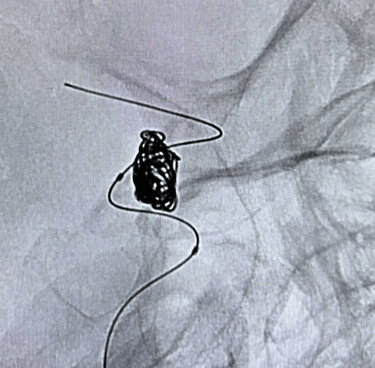

Neurocirurgia endovascular

Aneurisma cerebral;

Malformações arteriovenosas (MAVs);

Tratamento de doenças vasculares do cérebro e da medula espinhal por meio de técnicas minimamente invasivas — realizadas por cateteres, sem a necessidade de incisões cirúrgicas.